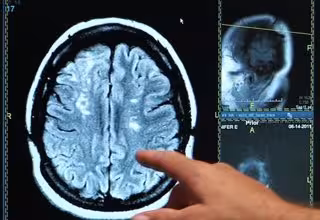

Ictus, derrame cerebral, cerebro

Ictus, derrame cerebral, cerebro - ONALD REAGAN UCLA MEDICAL CENTER - Archivo